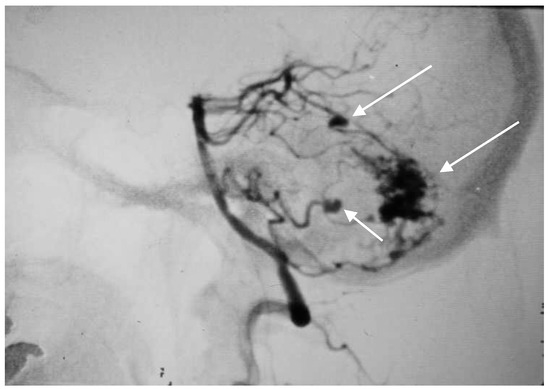

A 52-year-old woman presented with atypical headaches on an acute stage. MRI and subsequent PAG revealed an AVM of the cerebellar convexity with three aneurysms on parent arteries at the SCA and AICA bifurcations (Figure 3). The patient was treated by microsurgical clipping and resection of the AVM. Her postoperative course was uneventful, and follow-ups are undertaken every year.

Figure 3. Multiple superior cerebellar artery (SCA) and AICA aneurysms along with cortical arteriovenous malformation (AVM) of the cerebellum on lateral angiogram highlighted with arrows.